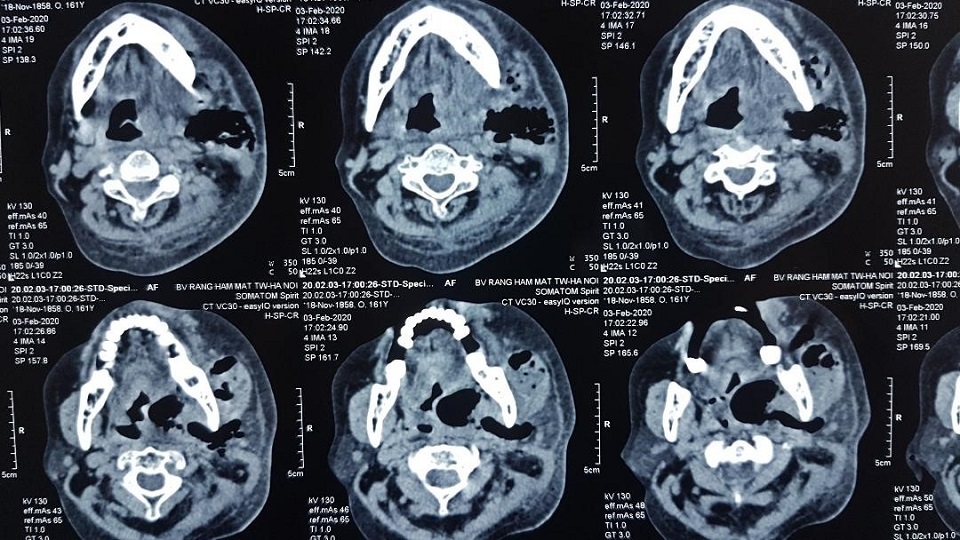

Tại bệnh viện, sau quá trình xét nghiệm, chụp chiếu phim, các bác sĩ chẩn đoán: bệnh nhân bị viêm tấy sàn miệng lan tỏa, cần nhanh chóng mổ cấp cứu.

Trong phòng phẫu thuật, kíp bác sĩ tiến hành rạch vùng dưới hàm người bệnh, lấy ra hàng trăm ml mủ bốc mùi, ổ mủ thông vào khoang miệng, lan xuống vùng cổ và có nguy cơ lan trung thất nếu không được xử lý kịp thời.

| Hình ảnh trước mổ và phim chụp của bệnh nhân với khối mủ lớn vùng cổ dưới hàm |